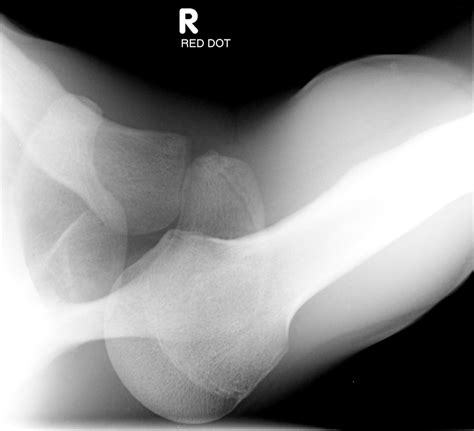

• Imaging Tests: X-rays are the primary imaging tool used to confirm the diagnosis. Additional tests such as CT scans or MRIs may be ordered to evaluate the extent of the injury and any associated damage to surrounding tissues.

• posterior dislocation shoulder xr